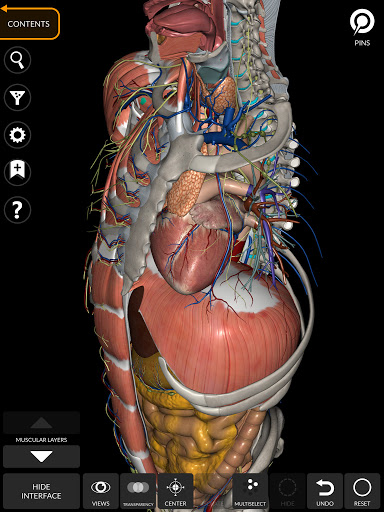

"Anatomy 3D Atlas" memungkinkan Anda mempelajari anatomi manusia dengan cara yang mudah dan interaktif.

Melalui antarmuka yang sederhana dan intuitif, Anda dapat mengamati setiap struktur anatomi dari sudut mana pun.

Model 3D anatomi sangat terperinci dan memiliki tekstur hingga resolusi 4k.

Pembagian berdasarkan wilayah dan tampilan yang telah ditetapkan sebelumnya memudahkan pengamatan dan studi bagian tunggal atau kelompok sistem dan hubungan antara organ yang berbeda.

MODEL ANATOMI 3D

saraf • Sistem pernapasan • Sistem pencernaan • Sistem urogenital (pria dan wanita) • Sistem endokrin • Sistem limfatik • Sistem mata dan telinga FITUR • Antarmuka yang sederhana dan intuitif • Putar dan perbesar setiap model dalam ruang 3D • Opsi untuk menyembunyikan atau mengisolasi satu atau beberapa model yang dipilih • Filter untuk menyembunyikan atau menampilkan setiap sistem • Fungsi pencarian untuk menemukan setiap bagian anatomi dengan mudah • Fungsi penanda untuk menyimpan tampilan khusus • Rotasi cerdas yang menggerakkan pusat rotasi secara otomatis • Fungsi transparansi • Visualisasi otot melalui tingkat lapisan dari yang superfisial hingga yang terdalam • Dengan memilih model atau pin, istilah anatomi terkait akan muncul • Deskripsi otot: asal, • Tampilkan/ Sembunyikan antarmuka UI (sangat berguna dengan layar kecil) MULTIBAHASA • Istilah anatomi dan antarmuka pengguna tersedia dalam 11 bahasa: Latin, Inggris, Prancis, Jerman, Italia, Portugis, Turki, Rusia, Spanyol, Mandarin, Jepang, dan Korea • Istilah anatomi dapat ditampilkan dalam dua bahasa secara bersamaan PERSYARATAN SISTEM • Android 8.0 atau yang lebih baru, perangkat dengan RAM minimal 3GB Reversi